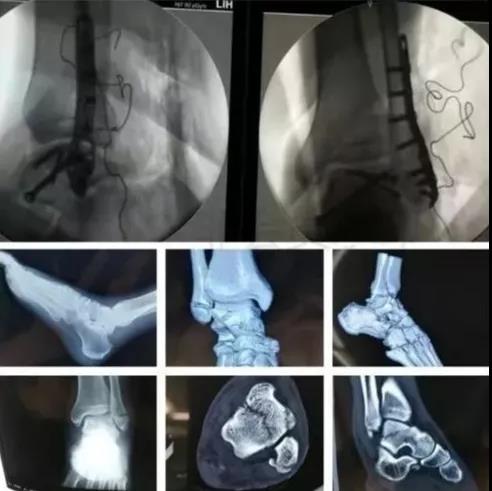

7)胫骨远端(pilon,踝部)

- pilon骨折,高能损伤,6-8h肿胀未形成,可以急诊做,手术时间<3小时。

- 10-14天,分步延期手术策略。

- 踝部骨折手术时机同样取决于皮肤条件。

8)足部骨折(距骨,跟骨,跖骨等)

高能损伤导致的距骨骨折并脱位,建议急诊做。